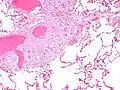

Gross pathology image showing sarcoidosis with honeycombing: Prominent honeycombing is present in the lower lobes accompanied by fibrosis and some honeycombing in the upper lungs. Honeycombing consists of cystically dilated airways separated by scar tissue resembling the honeycomb of bees. It is a nonspecific end stage of many types of interstitial lung disease.